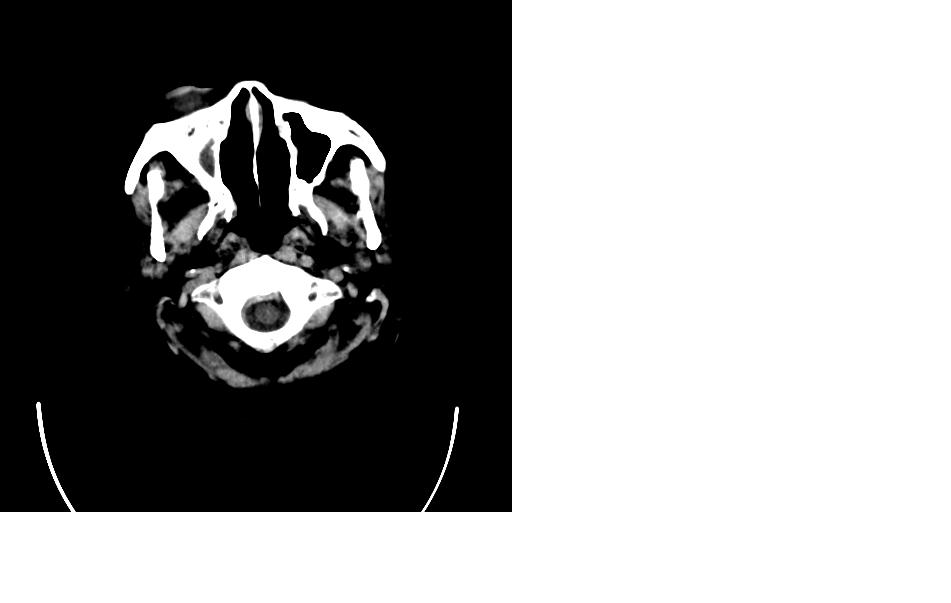

女,77岁,渐进性突眼2年,无其他明显症状

病变应起源于右侧额窦/或额骨板障,肿块周围骨包壳尚完整,呈膨胀挤压改变,右侧眼球受压移位,右侧大脑半球额叶白质受压塌陷,水肿不明显.考虑为良性病变,骨纤维瘤/或骨嗜酸性肉芽肿? 建议增强吧

支持:病变的起源我乐意定在右额窦。右额窦粘液囊肿或粘液腺癌累及筛窦、眼眶使眼球前突;向下进入颅内右额叶脑质及侧脑室受压变形。

右侧筛窦类圆形实质性肿块向颅内呈膨胀性生长,边缘较为光滑,其内似见囊性低密度影,边缘骨壁受压变薄移位,部分骨质缺损破坏

额骨右侧呈明显膨胀性骨质破坏,内外板明显变薄.考虑骨巨细胞瘤或动脉瘤样骨囊肿的可能性大。

定位:来源右额窦。定性:良性占位—额窦黏液囊肿。理由1、病灶中心位于右额窦区,侵及筛窦并向下向前压迫眼球2、骨质呈膨胀性改变,骨质弓形变薄但骨壳完整,如为恶性骨质应为侵蚀性破坏3、黏液囊肿好发于筛窦、额窦。